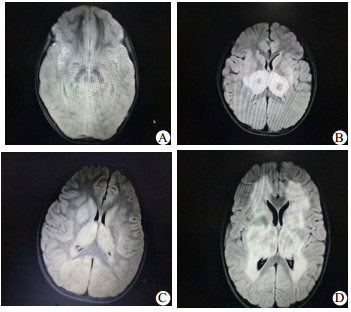

10例患儿入院前或入院时均积极完善头颅CT,头颅CT可见丘脑、基底节、脑干对称性低信号影(表 2)。4例患儿在入院后2~5 d完善头颅MRI,4例患儿头颅MRI提示病灶呈长T1长T2信号,FLAIR可见同心圆环状混杂信号(图 1)。通过完善呼吸道合胞病毒、肠道病毒、禽流感病毒核酸检测、支原体、衣原体、痰培养、血培养、脑脊液培养、尿培养病原学分析发现6例流感A阳性,5例核酸检测提示H1N1,1例核酸检测提示H1N3,1例流感B阳性,1例肠道病毒通用型阳性,2例相关病原学检测均阴性(表 1)。

#1 2 轻度 模糊 丘脑、脑干 5 图 1A 1

#2 0 弥漫 尚清 丘脑 3 图 1B 3

#5 1 弥漫 模糊 小脑 3 图 1C 3

#8 0 轻度 不清 丘脑、基底节 3 图 1D 3

A:病例1,患儿入院第3天诊断脑死亡,家属要求继续要求治疗,住院89天后家属自行联系康复科医院康复治疗;B:病例2,住院12天出院,没有遗留神经系统异常表现,出院时ADL评分Ⅰ级;C:病例5住院第3天拔出气管插管,住院15天出院,出院时神志转清,但不会讲话,有傻笑,需鼻饲喂养,康复中,ADL评分Ⅳ级;D:病例8,患儿住院第5天拔出气管插管,住院15天出院,出院仍处于昏迷中,昏迷评分7分,康复中,ADL评分Ⅳ级 图 1 四例患儿头颅磁共振结果

本组的10例患儿临床症状表现为感染后发热的1~3 d内出现神经功能迅速恶化,精神状态改变,迅速出现癫痫发作,从而进入昏迷状态,7例院外气管插管入科,2例入院后即刻需要呼吸机辅助呼吸。生化资料提示均存在不同程度的谷丙转氨酶、谷草转氨酶、肌酸激酶同工酶的升高。头颅影像学揭示了双侧丘脑的多灶性病变,此外,脑干、脑室、脑室周围白质和其他区域的变化可以存在。本组10例患儿均完善头颅CT,头颅CT都发现不同程度丘脑、基底节、脑干、小脑对称性低信号影;4例患儿完善头颅MRI,病灶呈长T1长T2信号,FLAIR可见同心圆环状混杂信号(图 1)。目前国内仅有个例报告,王华等[11]总结4例急性坏死性脑病,头颅MRI发现除了双侧丘脑对称性长T1、长T2信号外,大脑、小脑及脑干也有受累。